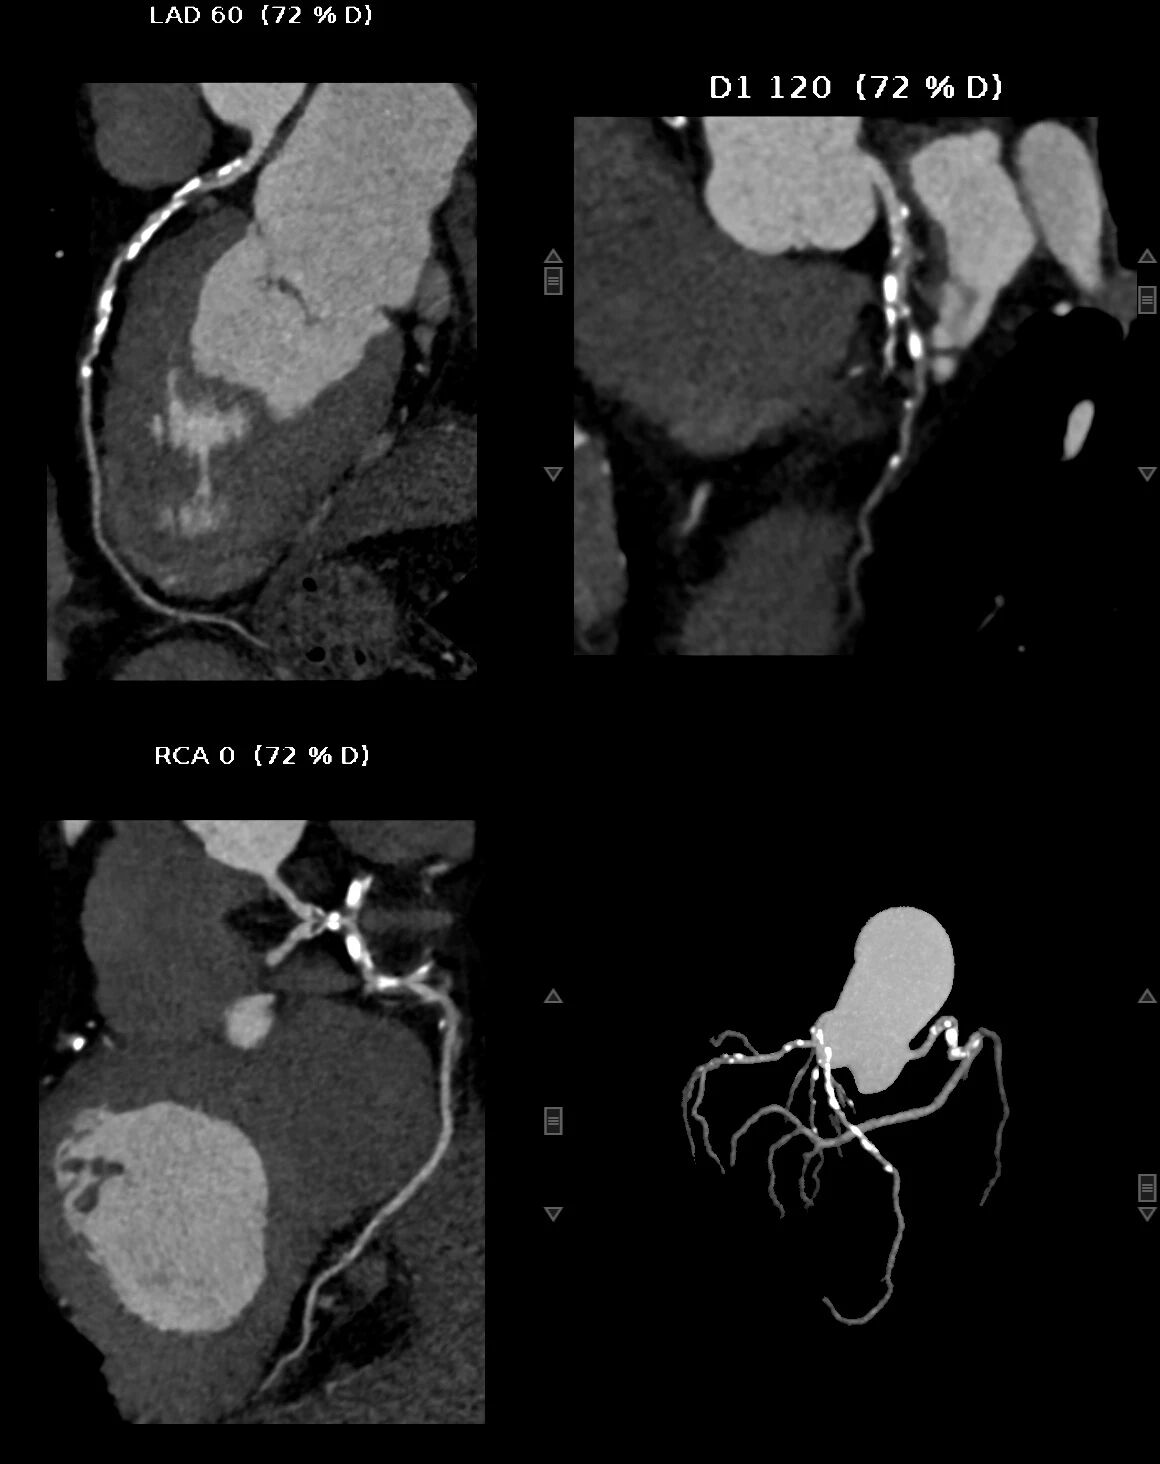

重度钙化的冠状动脉(MIP 图像)、黑色部分为钙化斑块